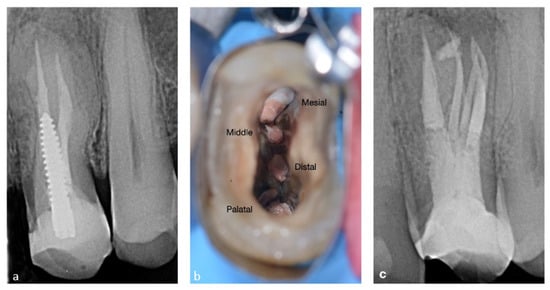

2.4. CASE 4